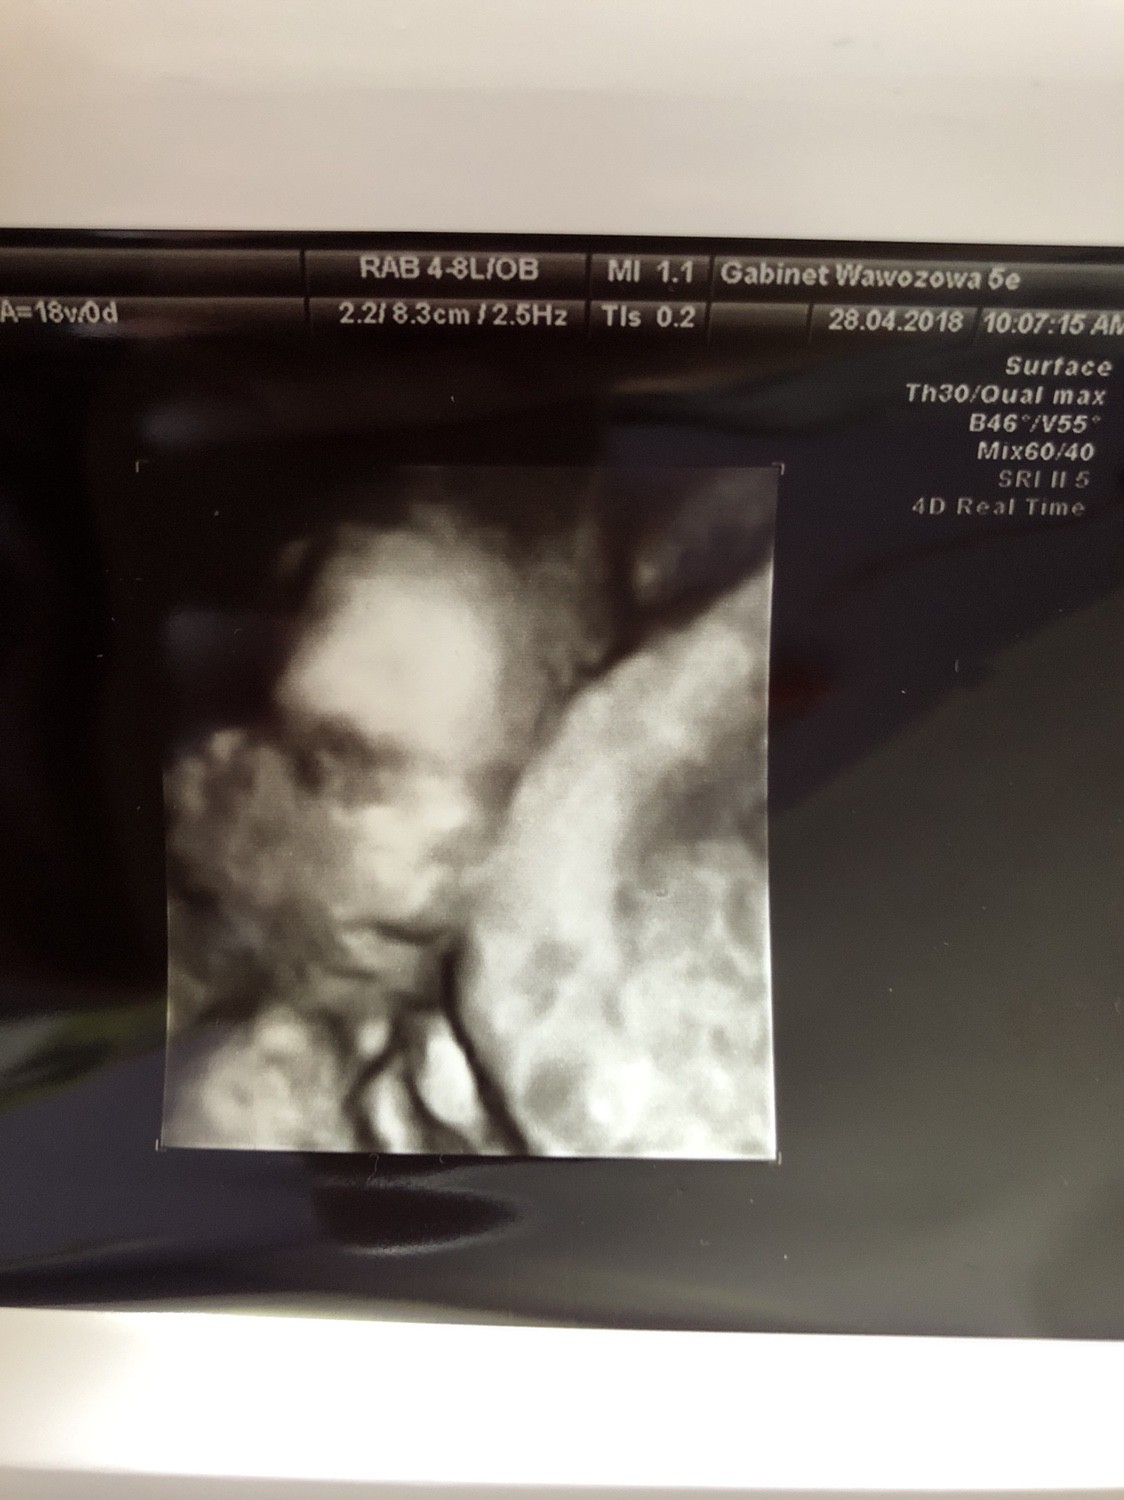

W końcu mogę napisać [emoji4] po wizycie wszystko dobrze, jednak chłopak pozostał chłopcem i po raz kolejny zrobił nam ekstra prezentację [emoji1] chyba będzie Czaruś[emoji4] wazy 203 g, czyli tak akurat [emoji4] machał rączkami i nóżkami na wszystkie strony, widzieliśmy słodka stopkę <3 szyjka ok,łożysko tylne( chyba, w każdym razie dobre, niezakłócające ruchów jakby co) [emoji1] mogłabym leżeć pod tym usg cały dzień [emoji1]

Załączam fotkę (to buźka jakby co [emoji14])